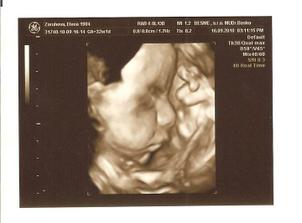

27.6. nedela - 3D ultrazvuk v HC, vsetko je ok, potvrdeny chlapec, nadherny zazitok

16.9. stvrtok - 4D ultrazvuk - Banovce nad Bebravou, MUDr. Baskova - vsetko ok, potvrdeny na 300% chlapec, 32tt+1 ale podla utz 32+5, vaha je cca 2000g, mame cca 30cm po kostrc, co by malo byt s nozickami asi 44cm